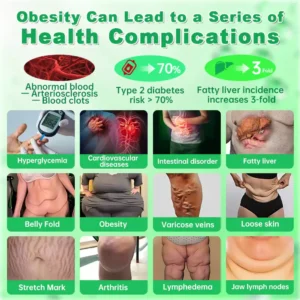

Are you troubled by health problems caused by obesity?

Health problems caused by obesity

The health problems caused by obesity are gradually taking away your vitality.

Cardiovascular Disease

Obesity increases the risk of high blood pressure, high cholesterol, and atherosclerosis, which can lead to heart disease, myocardial infarction, and stroke.

Respiratory Disorders

Obese individuals are more likely to experience sleep apnea, asthma, and impaired respiratory function.

Type 2 Diabetes

Excess fat, especially abdominal fat, can lead to insulin resistance, increasing the risk of developing diabetes.

Certain Cancers

Obesity increases the risk of colorectal cancer, breast cancer, endometrial cancer, and pancreatic cancer, which may be related to inflammation and changes in hormone levels.